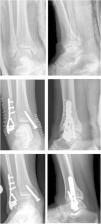

After a mean follow-up period of 33 months (12–73 months) after the fracture, all the patients were reassessed in the trauma clinic, where scores of the VAS scales at rest and during exercise were taken (from 0 no pain, to 10 the worst pain imaginable) of the American Orthopaedic Foot and Ankle Society (AOFAS) for the ankle and hindfoot (0–100) and of SF-36 as a general health questionnaire. Weight-bearing X-rays were also taken (AP and lateral) to determine the degree of tibioastragaline osteoarthritis; these were all assessed by the same surgeon using the osteoarthritis classifications of Takakura15 and Van Dijk16,17 (Fig. 2).

Progression to osteoarthritis was assessed using the Takakura and Van Dijk classifications, and we found that up to 18% of our patients had osteoarthritis with reduced joint space (Takakura type II). In no case did we observe a degree of osteoarthritis equal to or greater than a III in the Takakura or Van Dijk classification (Table 4).

If we attempt to relate tibioastragaline osteoarthritis with the joint surface affected by the fracture of the posterior edge, we can see that there is a relationship between the percentage of joint involvement with the development of osteoarthritis according to Takakura's classification, the more advanced the degree of osteoarthritis the greater the joint involvement (p=0.034). However, when we compared the three groups with each other we found no statistically significant differences in the development of tibioastragaline osteoarthritis, as this occurs even in patient with less than 10% joint involvement.